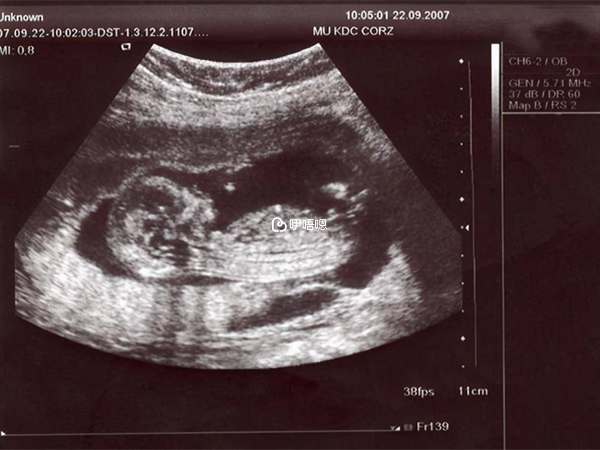

7月1日黨的生日,是個好日子,b超也很好,單胎,胎心胎芽也都有了。本以為是雙胎,不過人生何時是完美的,不奢求,一顆緊繃懸著的心也輕鬆些許,有了就好!